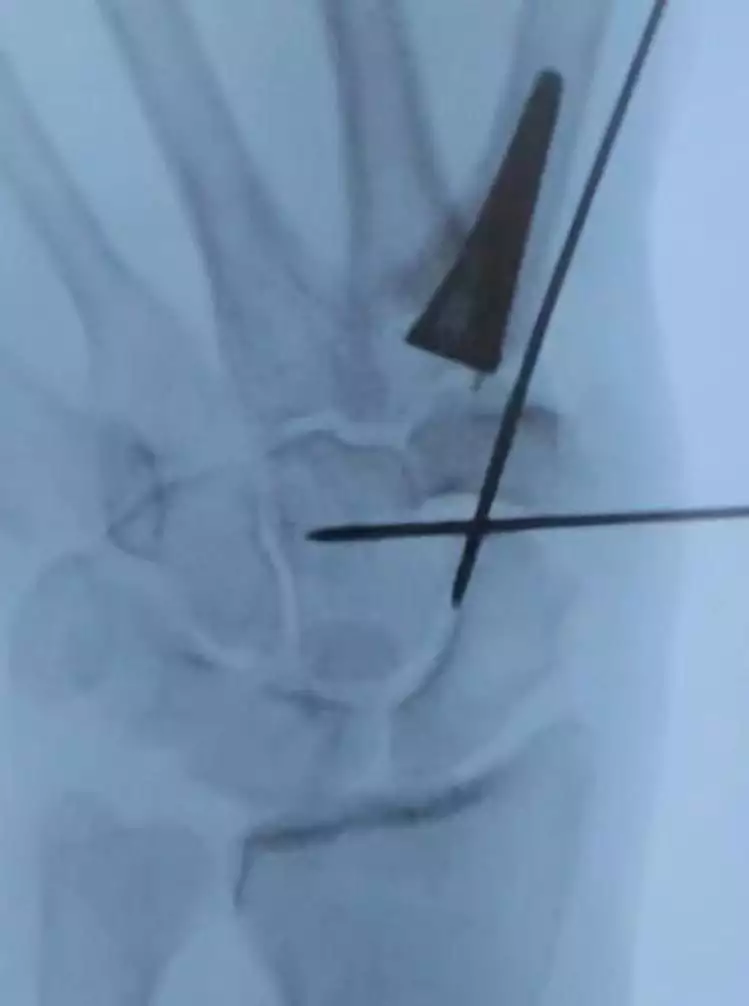

Die “TOUCH® DSG-Prothese” von Kerimedical ist eine Daumensattelgelenksprothese, die bei Arthrose des Daumensattelgelenks eingesetzt wird. Sie ist eine Weiterentwicklung der herkömmlichen Resektionsarthroplastik, bei der der Knochen (Trapezium) erhalten bleibt. Die Prothese zeichnet sich durch einen hochvernetzten Polyethylen-Einsatz aus, der eine hohe Verschleißfestigkeit aufweisen soll.

• Die Prothese besteht aus einem Metallteil, das am Mittelhandknochen befestigt wird, und einem hochvernetzten Polyethylen-Einsatz, der im Trapezium verbleibt.

Im Gegensatz zur Resektionsarthroplastik, bei der das Trapezium entfernt wird, bleibt es bei der TOUCH® Prothese erhalten.